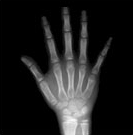

4) 같은 또래 아이들의 키보다 2표준편차 이상 작은 경우에는 성장클리닉 전문의의 진료가 필요합니다. 키가 정확히 또래 아이들보다 작은편인지 큰 편인지 진료를 통해 알아볼 수 있으며 성장판 촬영으로 골연령을 정확히 측정하는 것이 중요합니다.

| 열린경우 | 닫혀가는 경우 | 닫힌 경우 | |

| 지골 Phalange |

![]() |